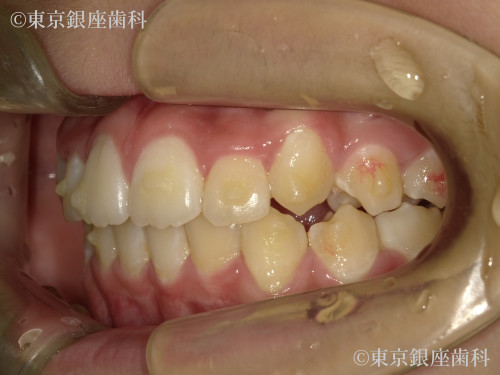

After

10代 女性

治療期間 11ヶ月 費用 65万円(税込)

インビザライン:ファースト